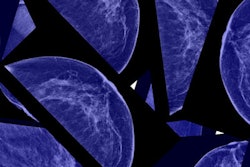

James also released a report that highlighted the need for DBT, which is not widely available to many low-income New Yorkers and New Yorkers of color -- the very women who may need DBT the most, as black women are more likely than white women to die from breast cancer, both nationally and in New York City.

In addition, Hispanic women have the lowest participation rate for regular mammography exams among any ethnic group in the country, and low-income women have higher death rates from breast cancer.

"We have a technology that could save lives, and it should be made available to all women," James said in a statement. "Putting DBT in our public hospitals would not only increase early detection among all women, but it would go a long way in closing the racial and economic survival gaps among women with breast cancer."